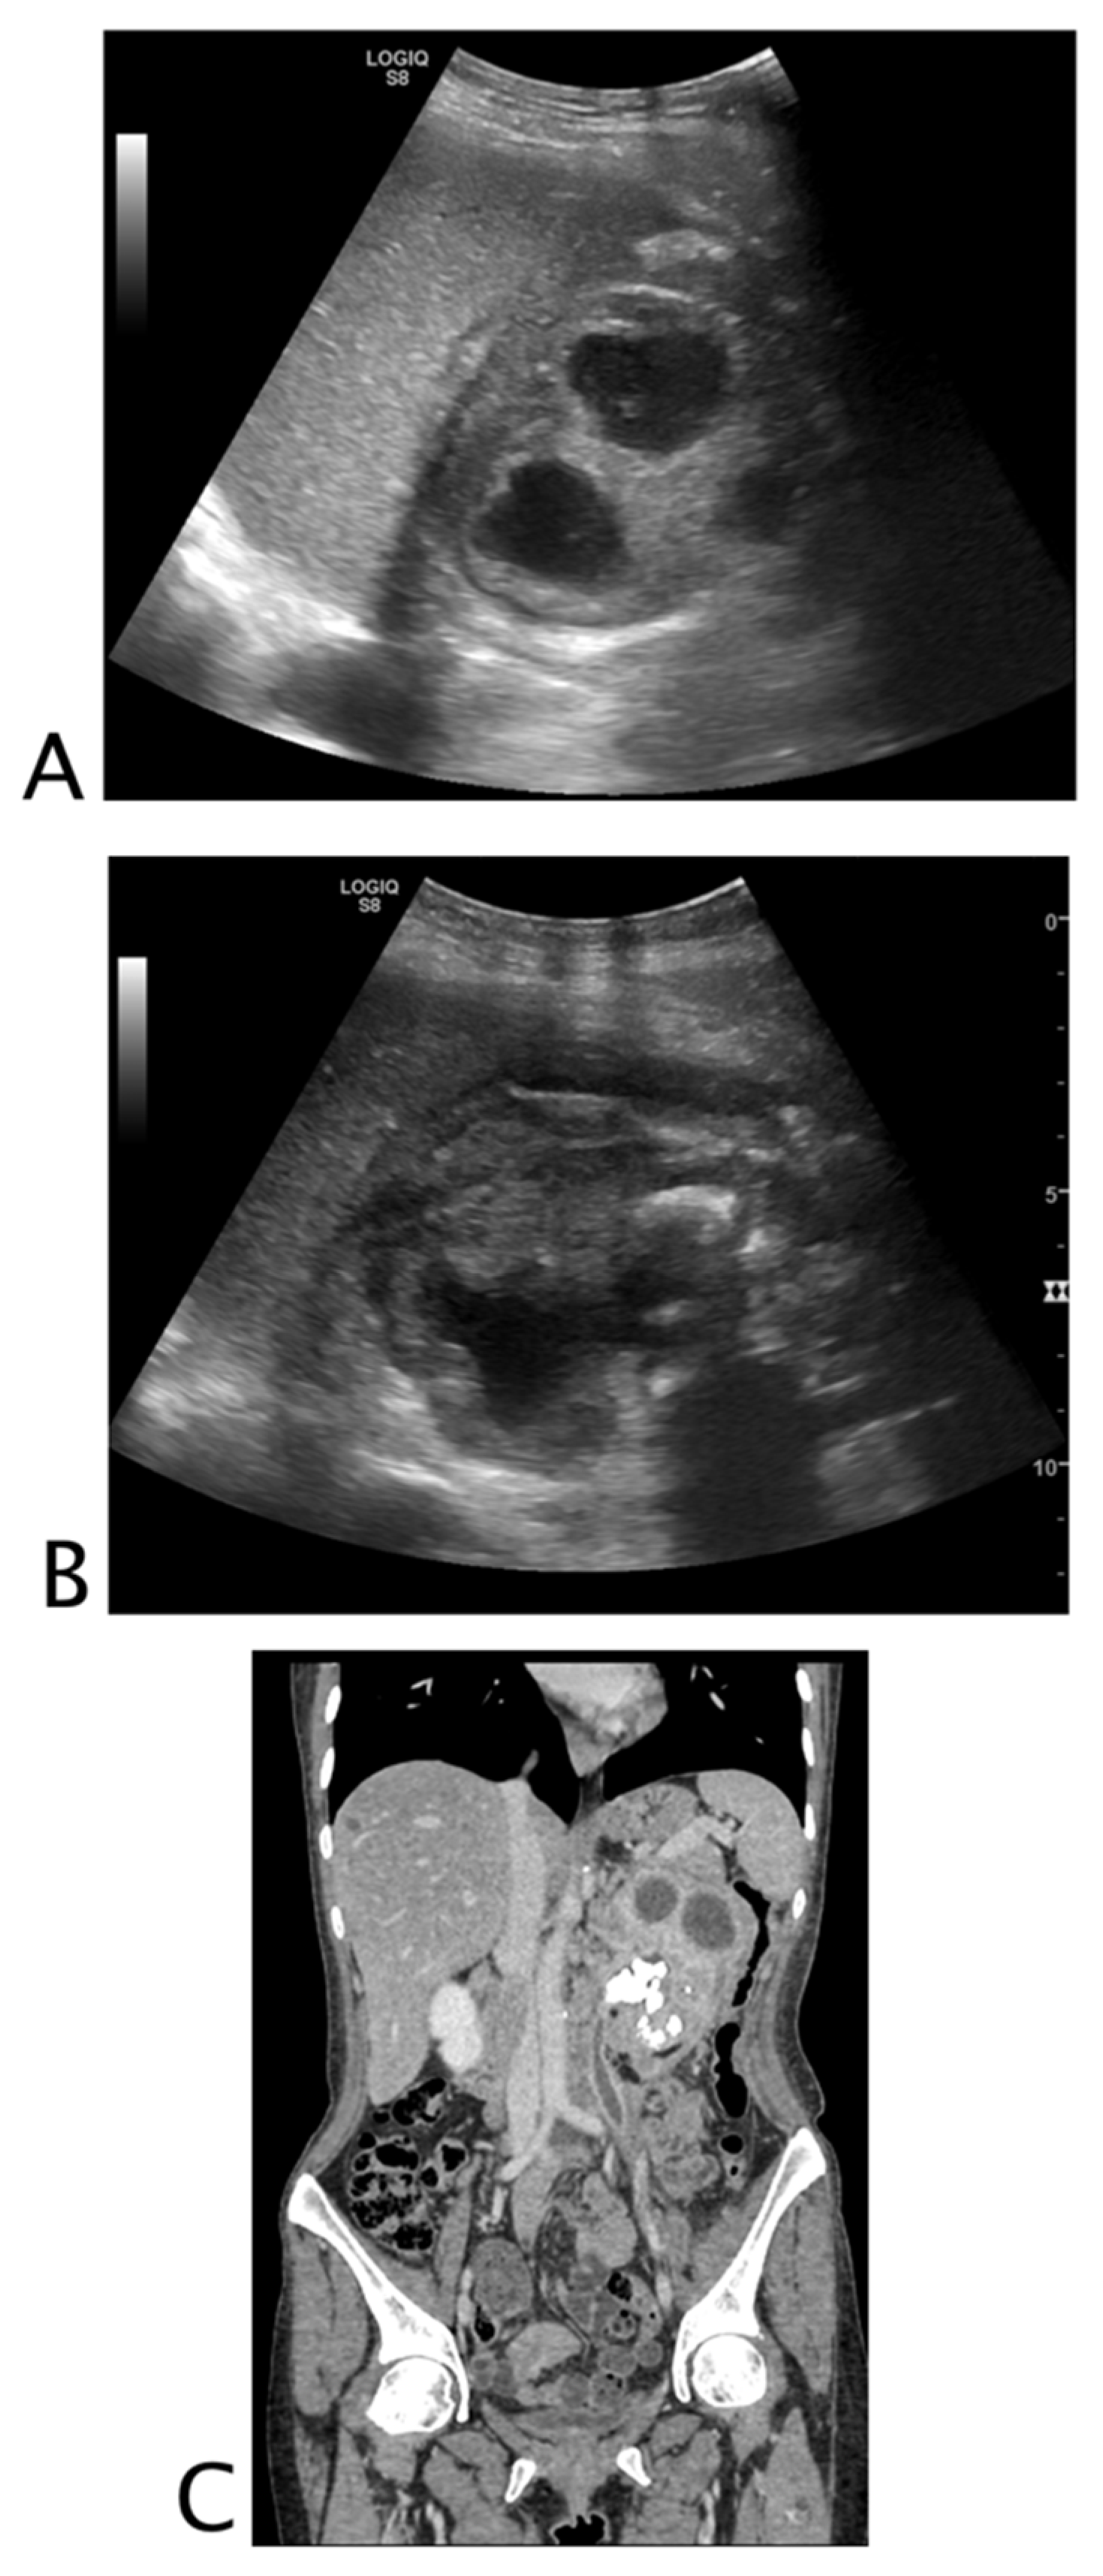

Intraparenchymal Fluid Lesions

| Intraparenchymal | Infected cyst Infectious cyst Hematoma Abscess Aneurysm Pseudoaneurysm |